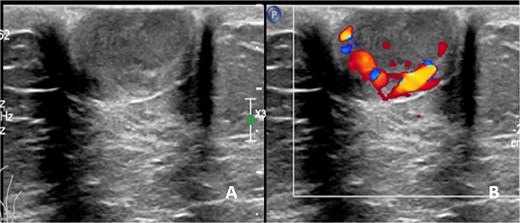

A 75-year-old female patient presented with left nipple pain and nipple discharge for one year. She denied any family history of breast or ovarian cancer, as well as any use of tobacco or hormonal drugs. Physical examination revealed a 1.5 × 1.5 cm firm, tender, and well-circumscribed mass at the left nipple, without skin or nipple retraction. The ipsilateral axillary lymph node was not palpable. While mammography was unremarkable, ultrasonography revealed a 1.7 × 1.5 cm oval, inhomogeneous hypoechoic mass with a predominantly vascularized rim (Fig. 1). An inflammatory mass, classified as BI-RADS 3, was considered.

Ultrasonographic finding of left nipple mass, (A) before applying color Doppler mode and (B) after applying color Doppler mode.